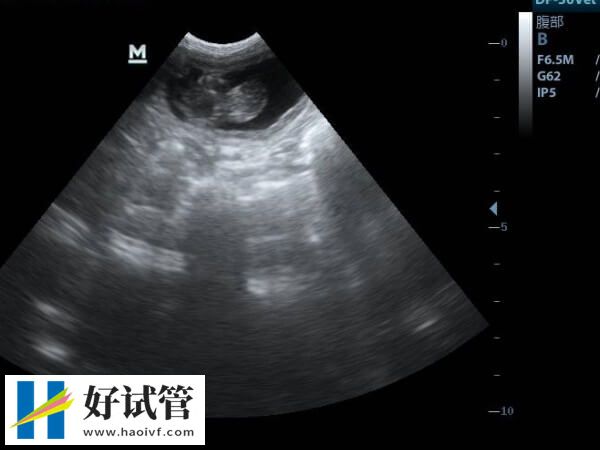

2、药物促卵及卵泡监测费用

在香港大学深圳医院进入到试管周期后,女方需要使用促排药物,由于个体的差异,每一个治疗者使用的药物剂量和使用药物的时间都不一样,这也就导致不同女性之间的促排费用差异化,通常情况下是年龄大的女性这一部分的花费相对要高一些,通常在10000-30000元左右。